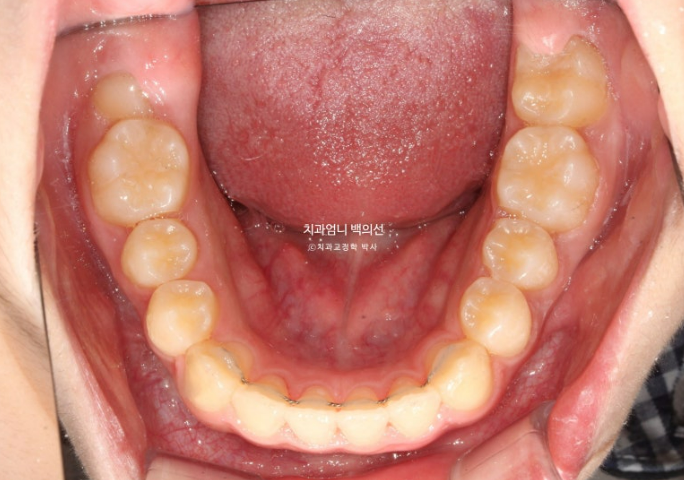

25년 5월 두번째 세트 21개 장치를 모두 낀 후 드디어 치료를 마무리 했습니다.

25.05

앞니 깊게 물리는 과개교합은 해결이 되었고 중심선은 잘 맞습니다.

어금니 교합은 1급 교합관계입니다.

결과가 성인교정에 준하는 만큼 유지장치도 성인교정에 준해서 들어갑니다.

과개교합 교정은 비베바를 하는 것이 좋지만 아직 제 2대구치 맹출중이라 인비절라인 투명유지장치 비베라는 맹출이 다 된 후 제작하기로 합니다.

24.03~25.05